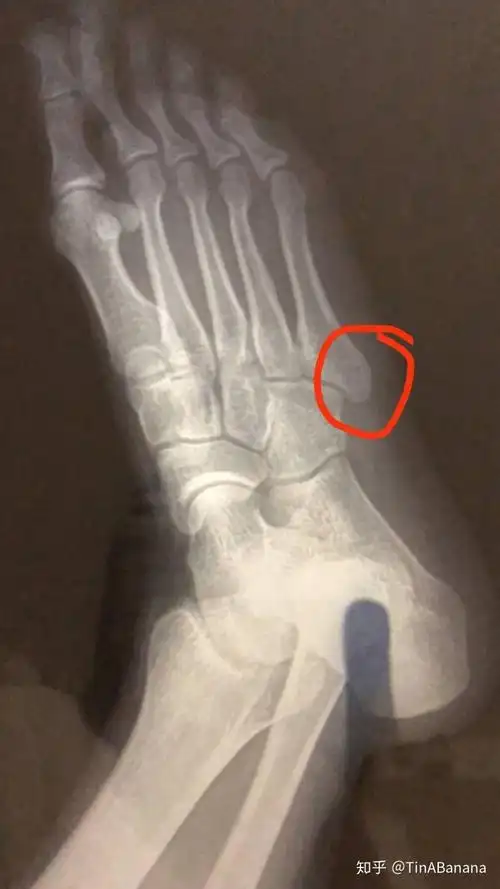

左足第五跖骨基底骨折

第5跖骨基地部破裂骨折第一天